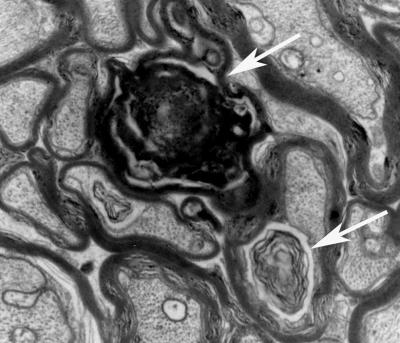

Nerve cells in people with Alzheimer's disease contain tangles — distorted clumps made up of the protein tau. Under normal circumstances, tau helps stabilize structures in nerve cells known as microtubules, which help transport nutrients and other substances from one end of the cell to the other. A growing body of evidence suggests the disruption in normal tau function during Alzheimer's disease could cause microtubules to break down, resulting in nerve cell damage.

In the new study, Brunden's group examined the effects of EpoD on older mice that already displayed memory deficits and tau tangles similar to people with Alzheimer's disease. The researchers, led by first author Bin Zhang, PhD, administered EpoD weekly to these older Alzheimer's model mice for three months before evaluating them. Compared with Alzheimer's mice that did not receive the treatment, the EpoD-treated mice had reduced formation of tau tangles in the brain. These mice also outperformed animals that did not receive the drug in learning and memory tests.